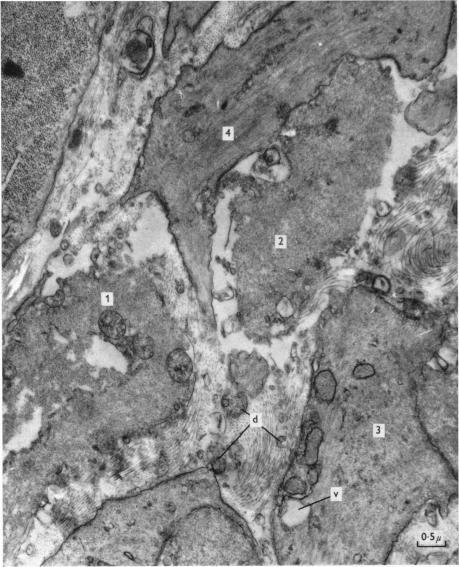

豚鼠盲肠带移植至眼前房后其生理及精细结构的变化

Changes in the physiology and fine structure of the taenia of the guinea-pig caecum following transplantation into the anterior eye chamber.

1. The taenia of the guinea-pig caecum has been used as a model to study the re-establishment of autonomic innervation following transplantation into the anterior eye chamber. The ultrastructure, the histochemical localization of noradrenaline and acetylcholinesterase and the pharmacology of transmission to the taenia have been examined 1 day to 16 weeks following transplantation. Both ganglion-free strips of the taenia and caecal wall segments including the underlying Auerbach's plexus were used.2. Caecal wall preparations: nerve fibres from intramural ganglion cells retracted during the first 2 days following transplantation, but reappeared in the muscle soon afterwards. Adrenergic nerves from the iris formed terminals about ganglion cells at about 2-4 weeks. Both cholinergic excitatory and non-adrenergic (;purinergic') inhibitory transmission to the muscle was re-established by 2-4 days following transplantation.3. Taenia strip preparations: both adrenergic and cholinergic nerve fibres were demonstrated histochemically in muscle bundles by 2-4 weeks. Non-adrenergic inhibitory and cholinergic transmission was not re-established until 2-4 weeks following transplantation. There was an abnormally dense re-innervation of the muscle by adrenergic nerve fibres by about 8 weeks which is compared with the innervation of aganglionic bowel in Hirschsprung's disease.4. The origin of non-adrenergic inhibitory responses in the transplanted taenia is discussed and the results considered in relation to the re-innervation of transplants of the vas deferens and of intestine during early development.

摘要

1. 豚鼠盲肠带已被用作研究移植到眼前房后自主神经支配重新建立的模型。在移植后1天至16周,对其超微结构、去甲肾上腺素和乙酰胆碱酯酶的组织化学定位以及向盲肠带的传递药理学进行了研究。使用了盲肠带的无神经节条带以及包括其下的奥尔巴赫神经丛的盲肠壁段。

2. 盲肠壁制剂:壁内神经节细胞的神经纤维在移植后的头2天内回缩,但随后很快在肌肉中重新出现。虹膜的肾上腺素能神经在约2 - 4周时在神经节细胞周围形成终末。移植后2 - 4天,向肌肉的胆碱能兴奋性和非肾上腺素能(嘌呤能)抑制性传递均重新建立。

3. 盲肠带条带制剂:移植后2 - 4周,在组织化学上可在肌束中显示出肾上腺素能和胆碱能神经纤维。非肾上腺素能抑制性和胆碱能传递直到移植后2 - 4周才重新建立。到约8周时,肾上腺素能神经纤维对肌肉的再支配异常密集,这与先天性巨结肠病中无神经节肠段的神经支配情况进行了比较。

4. 讨论了移植盲肠带中非肾上腺素能抑制反应的起源,并结合输精管和肠道移植在早期发育过程中的再支配情况对结果进行了考量。